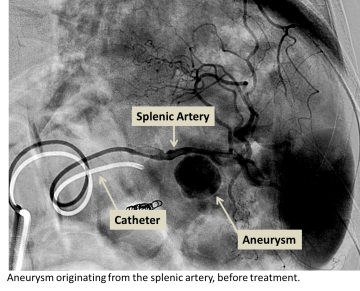

If the aneurysm is in a suitable location in the body and has specific dimensions, embolization is another treatment that may be considered.

• Aneurysm embolization is also performed by accessing the diseased blood vessel through a needle puncture in the arm or the leg.  A wire is navigated into the aneurysmal vessel using a fluroscope (x-ray machine) to guide the navigation.

• Once the vascular tree has been accessed, a catheter is placed over the wire and used to navigate to the aneurysm.  Embolization coils are then placed through the catheter into the aneurysm sac filling the sac and slowing blood flow into the sac.  Once blood flow within the sac becomes slow enough, the body’s natural clotting cascade causes clot formation within the sac and blood flow within the sac is stopped.

• Contrast may be injected into the vessel to test that the coil pack is properly seated and blood flow into the aneurysm sac is slow enough.  Once a satisfactory placement has been made, the wire and catheter is removed from the body and the puncture made in the arm or leg is sealed.  The patient is then taken to the recovery area for post-procedural observation.

Splenic artery aneurysm before treatment